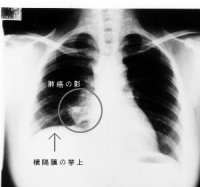

肺部常见的疾病有:气胸肺大泡肺气肿、肺部阴影(严格讲不算单独疾病,但临床上常作为多种肺部占位病变的统称)和肺癌等。

肺癌是最常见的肺原发性恶性肿瘤,绝大多数肺癌起源于支气管粘膜上皮,故亦称支气管肺癌。近50多年来,世界各国特别是工业发达国家,肺癌的发病率病死率均迅速

肺癌

上升,死于癌病的男性病人中肺癌已居首位。40多年前,在中国因肺部疾病施行外科手术治疗的病人中,绝大多数为肺结核,次之为支气管扩张、肺脓肿等肺化脓性感染疾病,肺癌病例为数不多。近30多年来,肺切除术的病例中肺癌逐渐增多,已跃居首位。据上海市恶性肿瘤统计资料,在男性癌肿病例中,肺癌发病率急剧增多,居第一位。